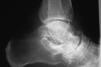

Según su posición en el plano sagital, el pie cavo puede ser anterior, posterior o mixto1. El pie cavo anterior es la forma más frecuente. En este pie el desequilibrio entre los músculos que traccionan el pie tiende a verticalizar los metatarsianos, principalmente el primero, lo que hace que sus cabezas se hallen marcadamente descendidas con referencia al talón. Esta desnivelación se observa en el pie de perfil y sin apoyar, y el plano en que se hallan las cabezas de los metatarsianos es inferior con relación al del talón (fig. 4). Los dedos están en garra, con la primera falange en hiperextensión y la segunda en flexión forzada, debido a la atrofia y el acortamiento de lumbricales e interóseos, que dejan de estabilizar y flexionar la articulación metatarsofalángica de los dedos trifalángicos y de extender las interfalanges, con lo que la acción del flexor de los dedos hace progresiva la deformidad1. El pie cavo posterior aparece en la parálisis del tríceps sural y, como consecuencia de la falta de tracción del Aquiles, el calcáneo se verticaliza y asciende por su parte anterior. Las formas mixtas se presentan cuando la caída del primer metatarsiano es más acusada respecto de los demás, pues el retropié se coloca en gran supinación para compensarla y secundariamente el calcáneo se verticaliza.

Figura 4. Pie cavo. Antepié en equino con relación a retropié. Dedos en garra.